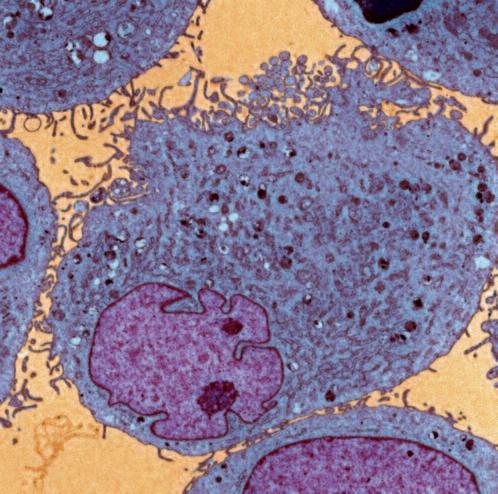

Immagine al microscopio di cellule leucemiche. Le sfere rosse del pacmen rappresentano gli enzimi collagenasi.

Questo vale anche per le cellule leucemiche. Una caratteristica di questa forma di tumore del sangue è l’eccesso di produzione di globuli bianchi, i pazienti affetti da leucemia muoiono principalmente, perché queste cellule bloccano la circolazione del sangue. In molti casi i leucemici muoiono per il cedimento di vari organi, in particolare ‘gli organi filtro’: il fegato e la milza. Milioni di globuli bianchi invadono questi organi attraverso il flusso sanguigno. Queste cellule cancerose producono immense quantità di enzimi che digeriscono il collagene, digerendo letteralmente questi organi dall'interno.

La foto nella pagina a fianco mostra una sezione trasversale al microscopio del fegato di un paziente con ‘leucemia linfatica’. Ciascuno dei piccoli puntini viola nella foto è un globulo bianco (in questo caso linfocita) che ha invaso il tessuto del fegato (aree rosa).

Considerando l’enorme quantità di questi puntini viola e il numero di enzimi che assimilano il collagene che ciascuno produce, è facile prevedere l’ingente distruzione del tessuto connettivo e il danno apportato all’organo da questo tipo di cancro.

La leucemia è un buon esempio di come la comprensione dei meccanismi delle cellule tumorali, la produzione di enzimi che digeriscono il collagene da parte dei globuli bianchi, per poter studiare terapie efficaci.

Immagine al microscopio della leucemia linfatica

Globuli bianchi affetti di cancro (linfociti) invadono il fegato L’enorme quantità di collagenasi prodotte da queste cellule distruggono l’organo e causano insufficienza epatica.